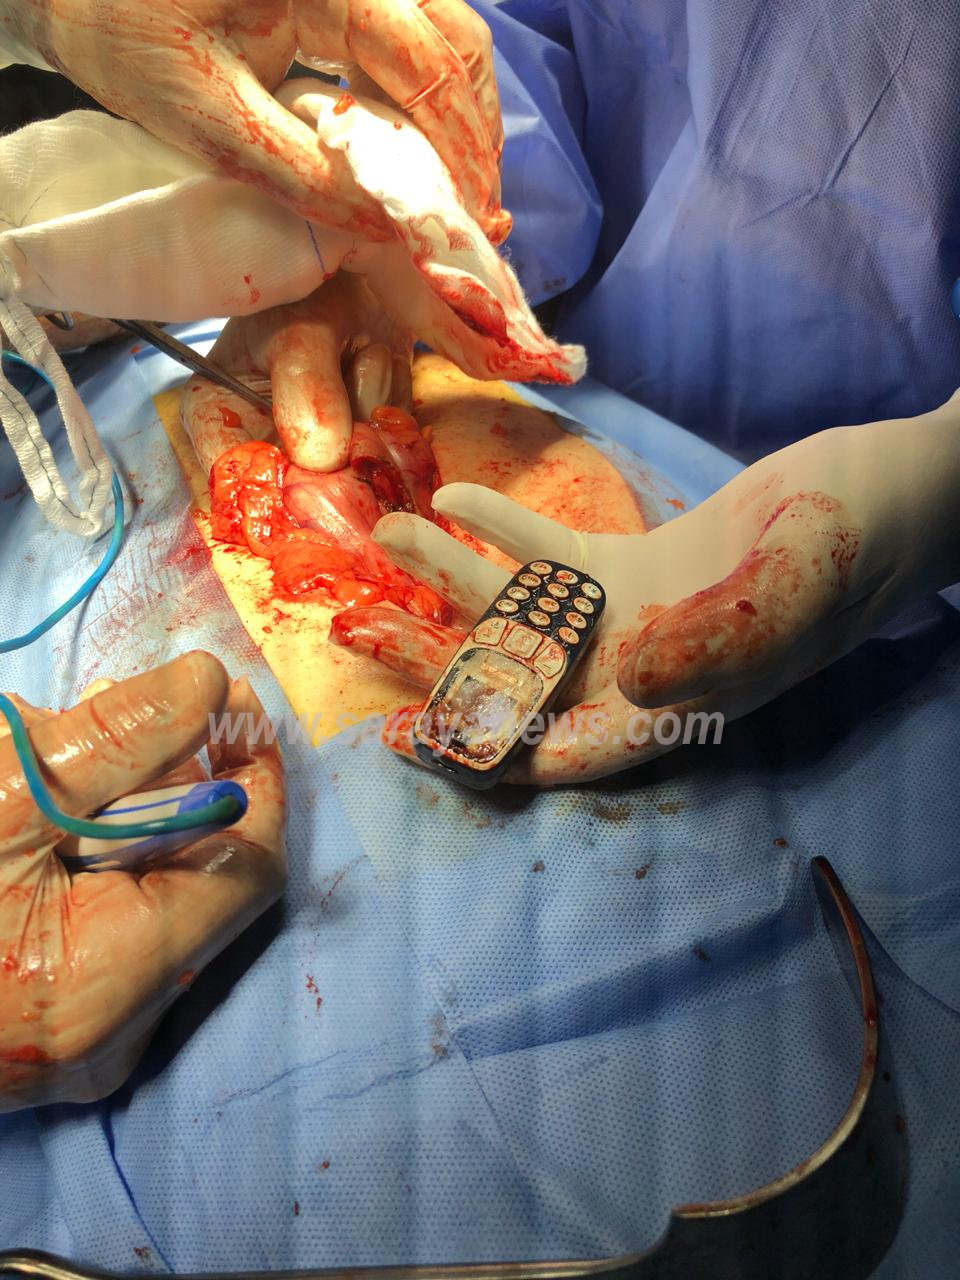

ولفت المصدر ، انه تم استدعاء رئيس قسم الجراحة الدكتور نايف العبدللات وفريقه الجراحي لمحاولة استخراج الهاتف ، حيث تم اجراء عملية جراحية لاستخراج الهاتف بعد فشل عملية التنظير.

واشار المصدر الى ان المريض قام بادخال الهاتف والبطارية عن طريق الفم ، وذلك من اجل الحصول على المال ، حيث ان الدقيقة الواحدة التي يجريها السجين داخل السجن تتجاوز الدينار بين المساجين ، الا انه خاطر بحياته ،وكاد ان يتسبب بقتل نفسه ، لولا تدخل الاطباء بالصورة العاجلة .